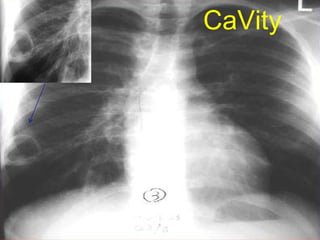

Cavitating lesion

CaVity